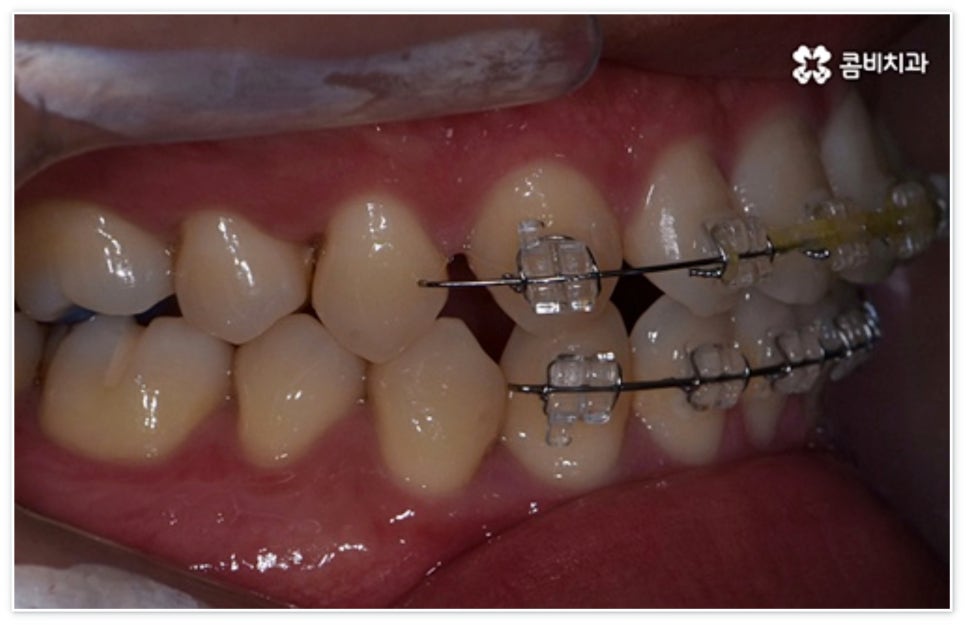

환자분들에 따라 다르지만 통상적으로 전체 교정이 1년에서 2년 반 정도 소요된다면 부분 교정은 6~8개월 정도로 기간 단축이 가능하여 치료에 대한 부담을 줄일 수 있으며 대부분 발치 과정 없이 필요한 부위에만 브라켓을 부착하는 만큼 불편함이 적고 구강 관리도 용이한 편이니 (사진에서 살펴볼 수 있는 케이스) 이에 대해서 자세히 알아보시면 좋을 거예요. 물론 누구나 가능한 것은 아니고 개인의 구강 상태에 따라 진행을 해야 하므로 꼼꼼한 검진과 충분한 상담부터 받아보시길 권유드리고 있습니다.